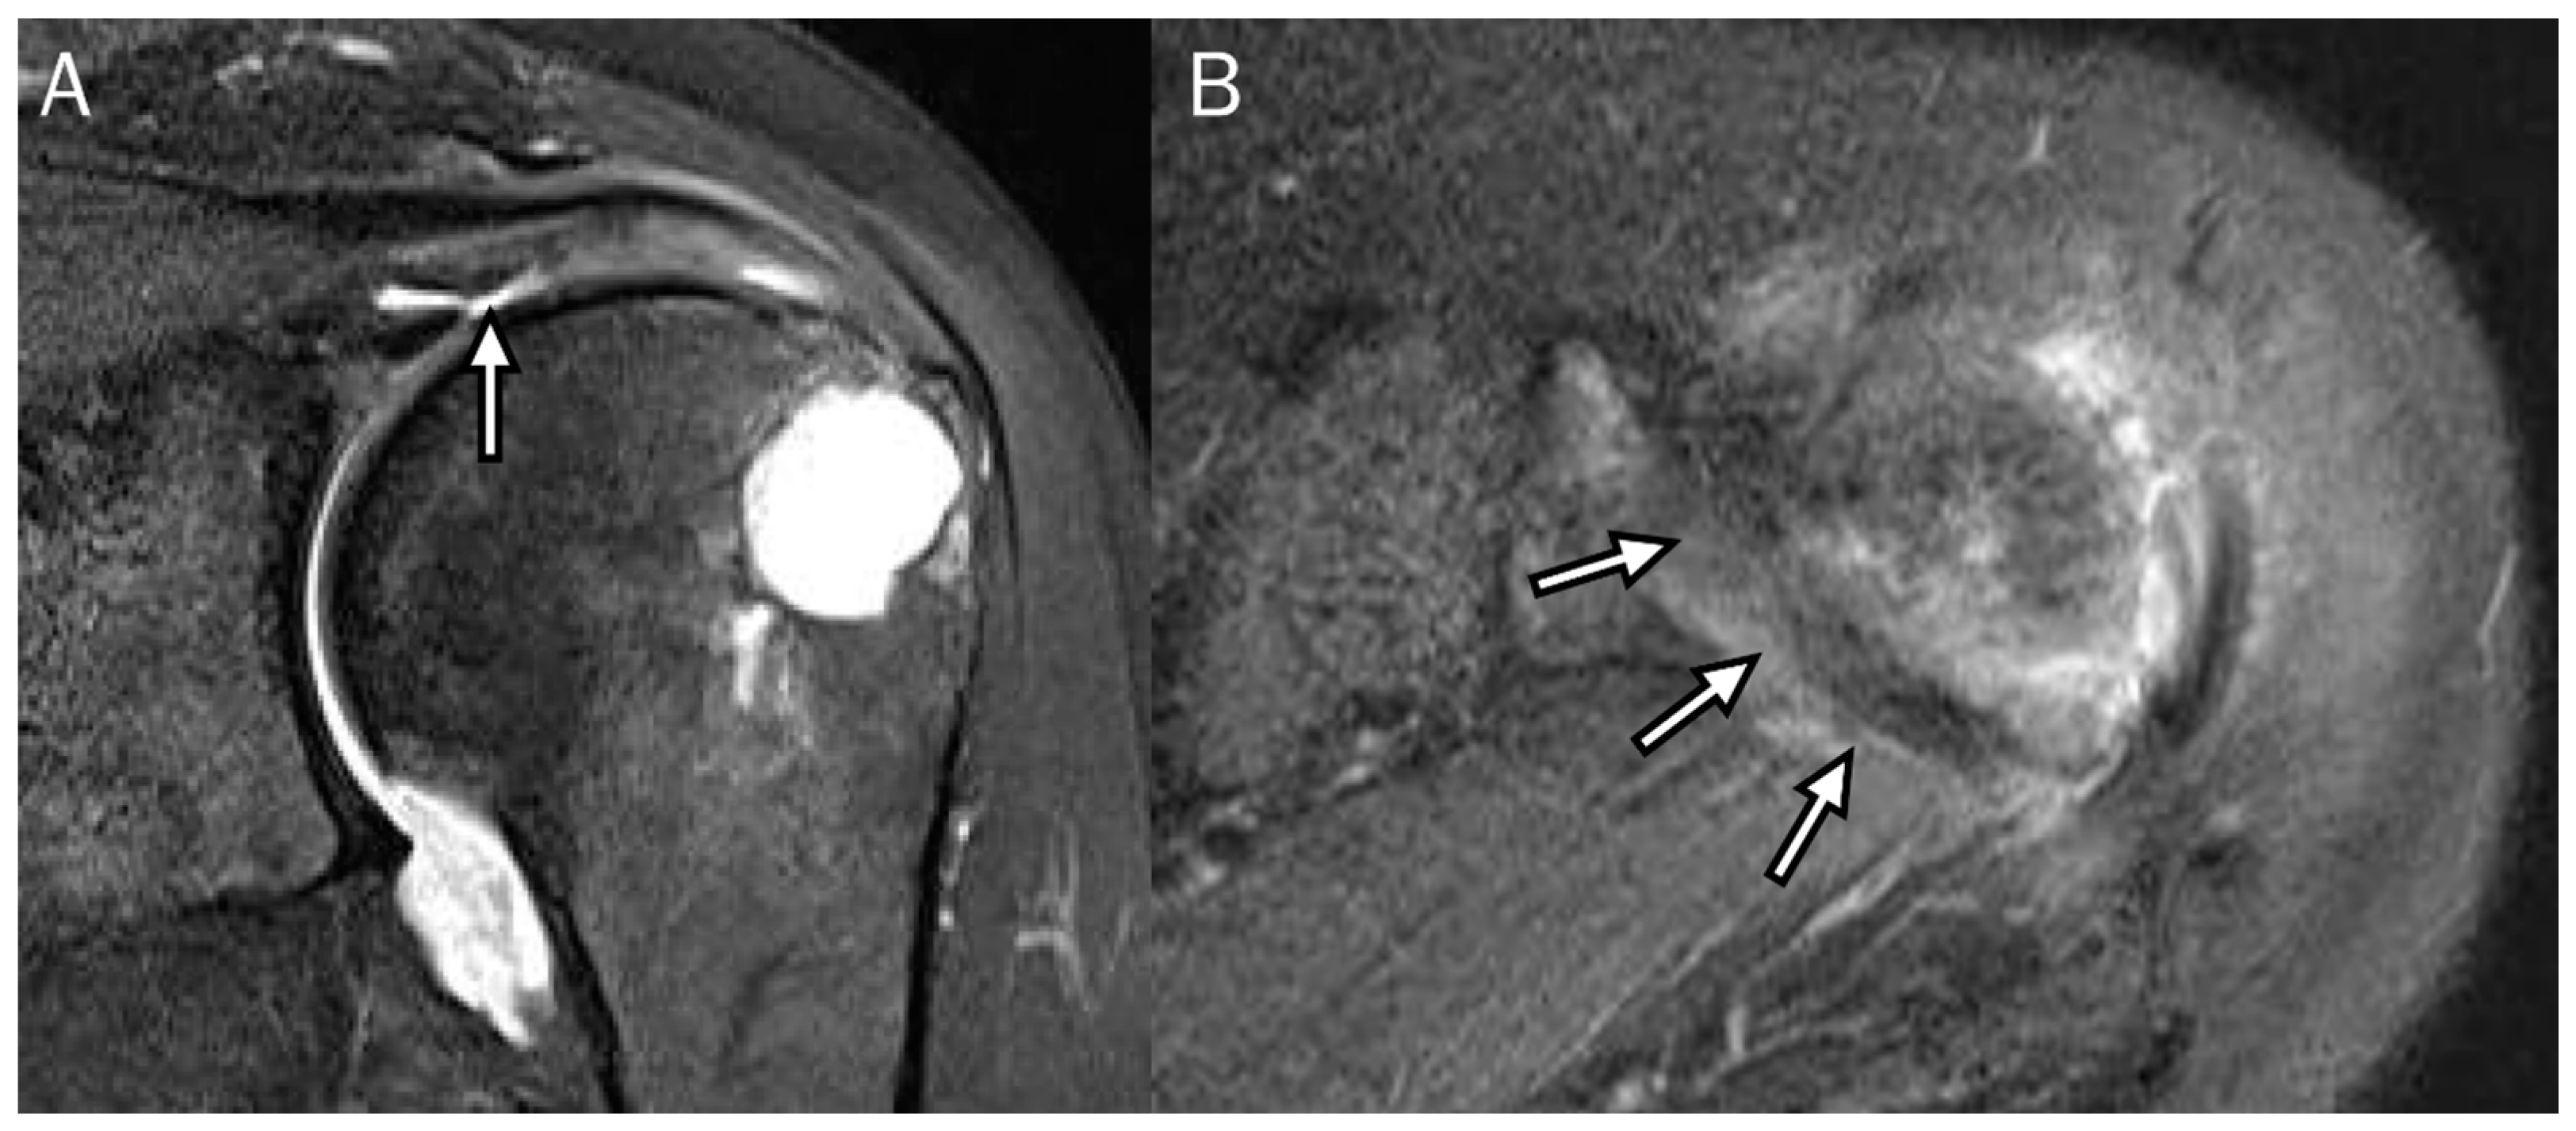

4. Radiologic Definition and Classification Using MRI

5. Radiologic Diagnosis of Delaminated Tears Using MRI